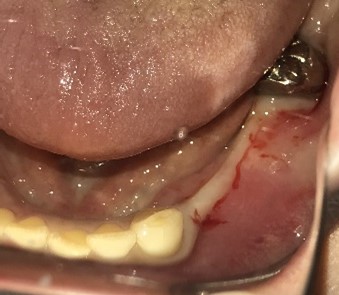

【インプラント埋入前】

冠はブリッジを切断しただけで取れてきました。軟化象牙質を取り除いたところ、歯根しか残っていない状況で保存できるかどうかのぎりぎりのところでした。